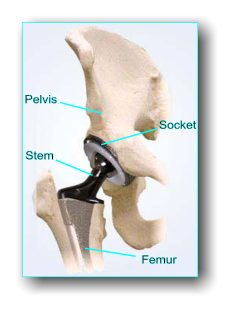

Pelvis Stem Socket Femur